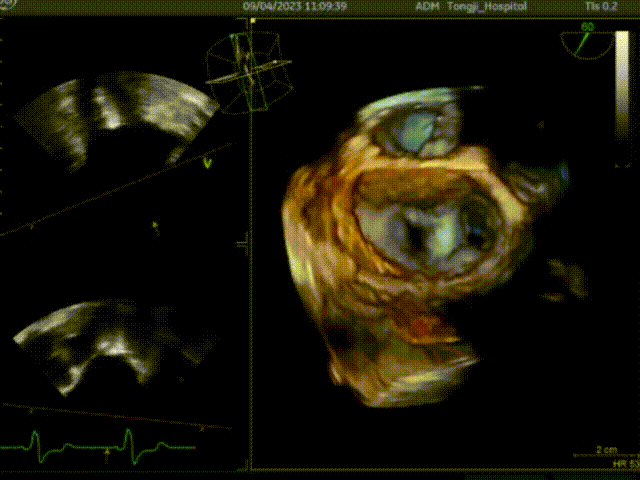

二、行经心尖介入二尖瓣夹合手术ValveClamp

ValveClamp抓捕瓣叶并收入闭合环内